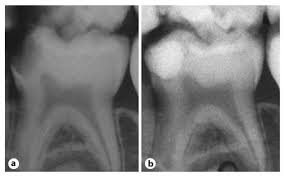

نقش عکس رادیوگرافی در تشخیص

گاهی علائم بالینی بهتنهایی کافی نیست. دندانپزشک با گرفتن عکس رادیوگرافی (پریاپیکال یا بایتوینگ) میتواند عمق پوسیدگی، نزدیکی آن به عصب و وجود عفونت در انتهای ریشه را بررسی کند. در بسیاری از موارد، تصمیم نهایی بین پر کردن یا عصبکشی دقیقاً بر اساس همین تصویر گرفته میشود.